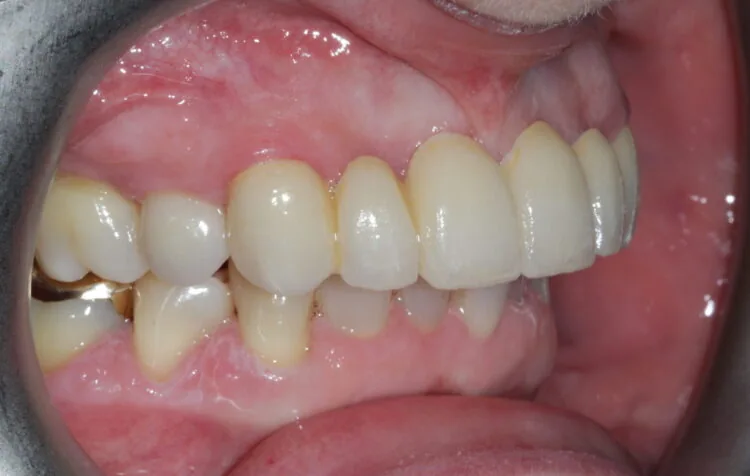

4. After this phase, a definitive six-unit porcelain bridge was placed to restore aesthetics and function.

5. To complete the smile enhancement, porcelain veneers were placed on the premolars to increase the buccal corridor fill and broaden the smile.

Outcome

The final result delivered a dramatic transformation. The bridge and veneers blended naturally, restoring symmetry and confidence to the patient’s smile. Upon seeing the result for the first time, the patient was visibly emotional and described the outcome as far exceeding her expectations.